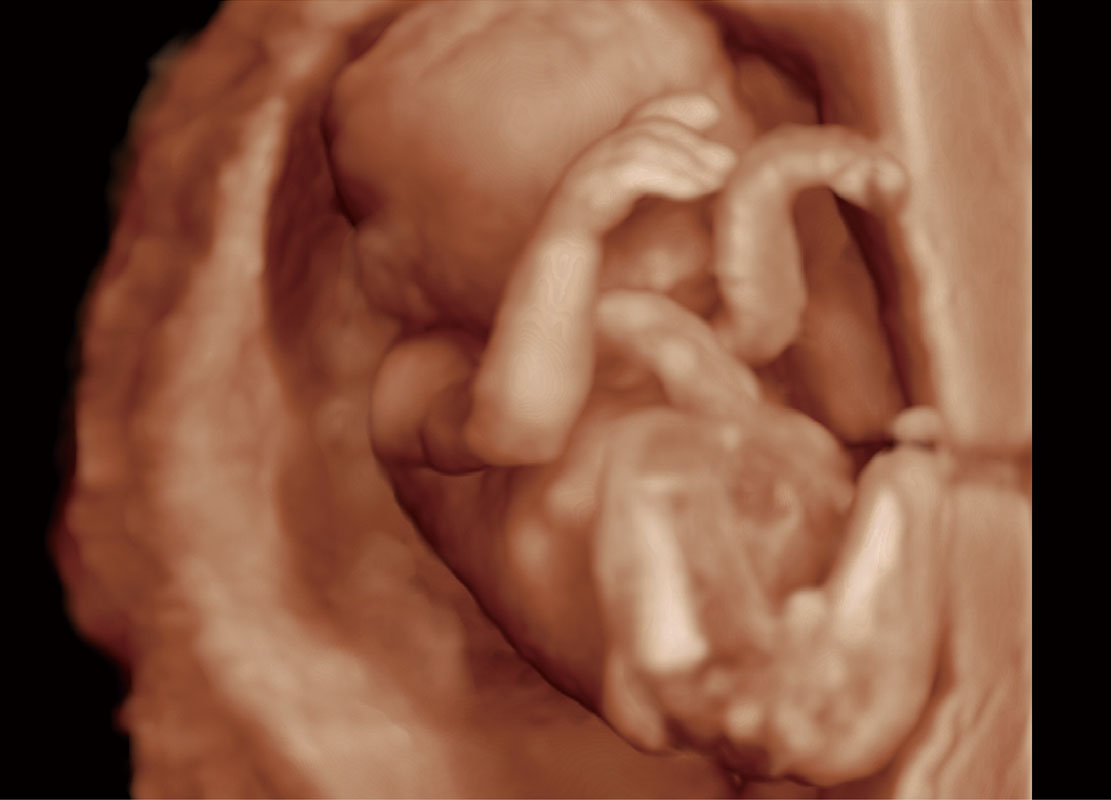

P60在胎儿早孕期超声筛查中为您带来优异的图像质量。

• 早孕-胎心

• 高分辨率容积成像-早孕胎儿